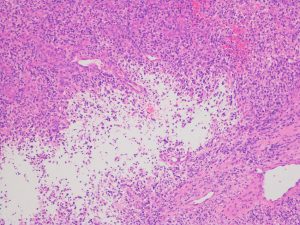

退形成性性星細胞腫に似た膠芽腫の病理診断(画像は拡大できます)

核の異形成が目立ち分裂像が見られ脳実質へのびまん性浸潤があります。これだけでは,退形成性星細胞腫 グレード3のようにみえます。

血管内皮細胞の高度の増殖(左側)endothelial proliferation があり,腫瘍細胞はGFAP陽性です。

ごく一部に壊死像(右側)が認められて,Ki-67標識率は40%に達します。総合的にはグレード4と診断されます。

さらに,シーケンスでIDH-1 R132 wild type, IDH-2 R172 wild type,免疫染色でolig 2陽性,p53陰性,ATRx陰性,MGMT 1+ (0-4+),FISHで1p/19q codeletion (-)を確認しました。

膠芽腫の病理診断ではこのくらい面倒な病理診断をします。2020年,残念ながら保険診療ではカバーできないので,病理診断医の無償の協力となっています。